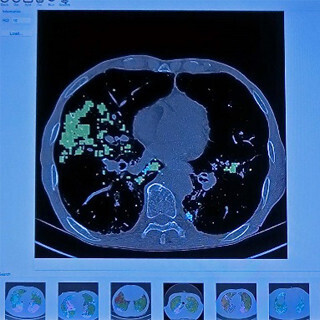

Vuno IncはCTやMRI、X線画像などをDeep Learningで処理して診断を行う「VUNOnet」を提供している。医者や病院での画像診断をより短時間で、より正確に行うことができるという。

このような診断では人間の医師でも経験を積まないと画像を読むのは難しいと言われるが、Deep Learningで正常な部分と病変のある部分を区別し、病変のある部分は見やすいようにその種類で色を変えて塗り分けている。